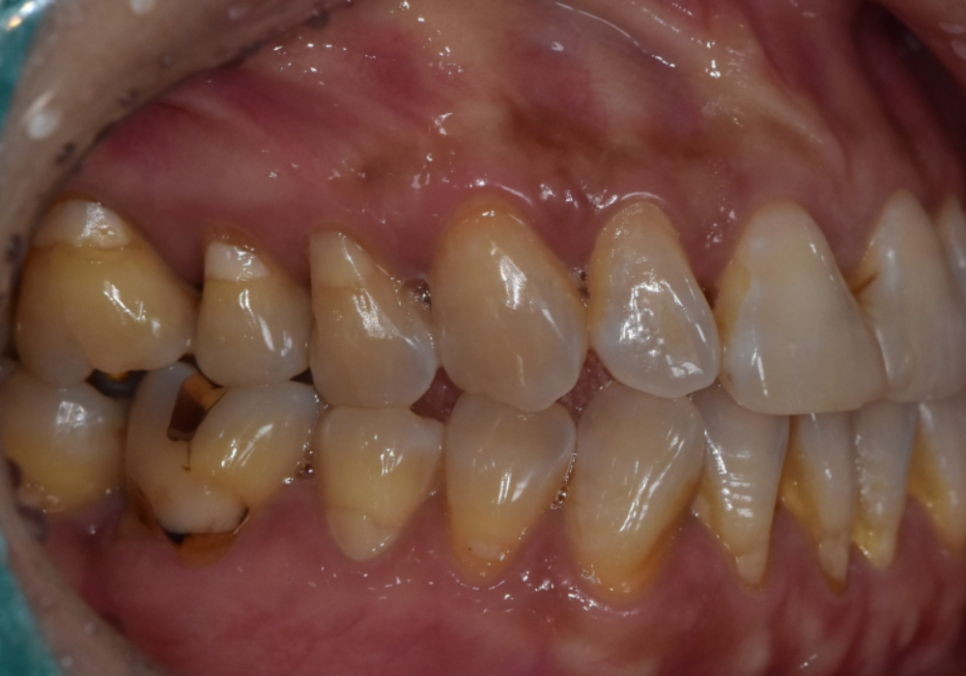

레진 재치료보다 라미네이트를 선택한 이유

고덕동 치과 누런 이, 앞니 사이 틈, 잘못된 관리 때문일까?

앞니 사이 틈과 치아 변색을

함께 개선하기 위해

레진 재치료도 고려할 수 있었지만,

잇몸이 더 내려가면

다시 틈이 생길 가능성이 높고

레진은 시간이 지나며

변색과 마모가 비교적 빠른 편이기 때문에

이번 경우에는

라미네이트 치료가 더 적절하다고 판단했습니다.

라미네이트는

얇은 세라믹 보철을 치아 겉면에 부착해

치아의 색상과 형태를 함께 개선할 수 있어,

블랙 트라이앵글과 치아 변색을

동시에 보완할 수 있는 치료 방법입니다.